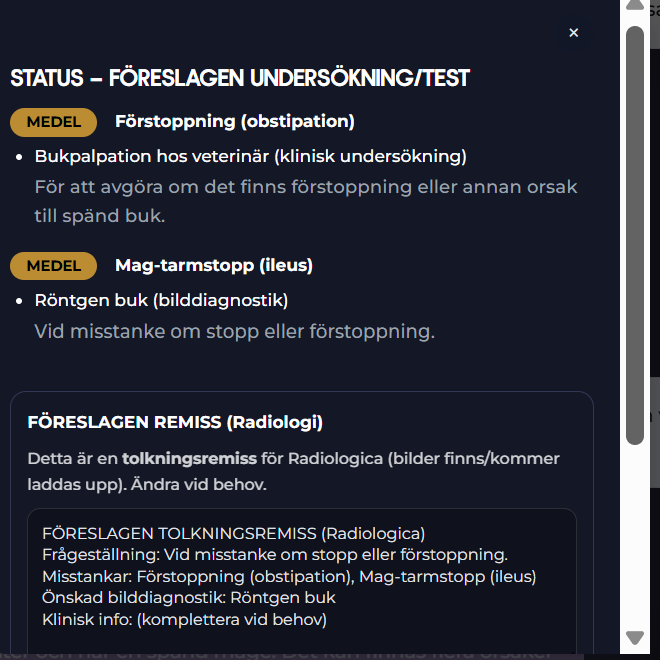

Exempel på Föreslagen Diagnostik från Radiologica - Röntgenremiss

Radiologica Röntgentolk har utgått från chatt med din doktor som har en frågeställning som ska utredas. I detta exempel är det en katt som kan vara förstoppad. En komplett remiss har producerats. Remissens frågeställning tillsammans med röntgenbilder du kan ladda upp kommer att tolkas och generera ett remissvar.